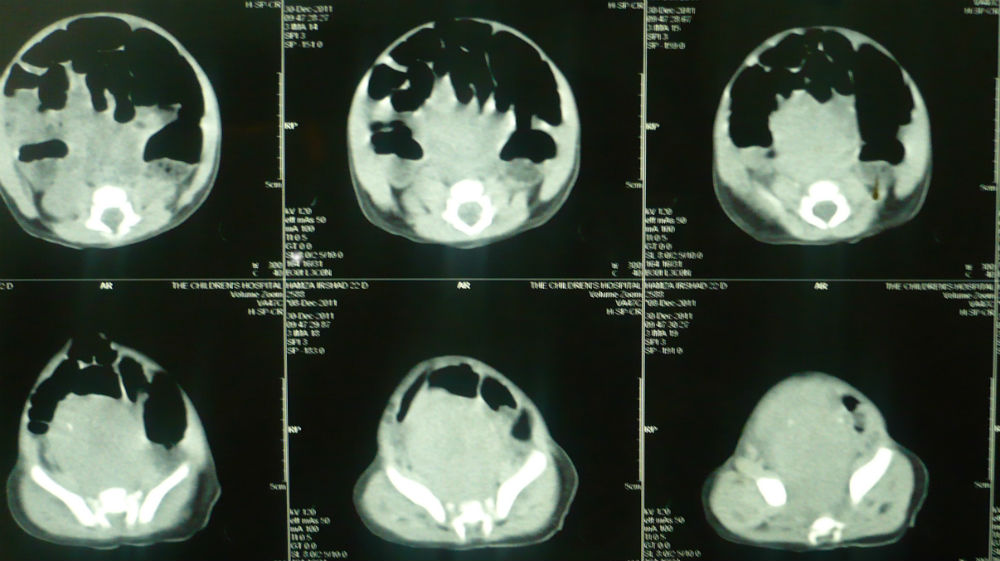

Two most important lesions that may have calcifications are type-IV SCT and neuroblastoma; but, the surgical approach to both of these lesions is different as SCT requires coccygectomy in addition to the mass excision through another incision on the buttock. On the other hand, coccygectomy and another incision are avoidable in case of neuroblastoma and other lesions at the same location. Therefore, further work including tumor markers like alpha fetoprotein (AFP) or β-HCG should be performed and interpreted with reference to the age of neonate as AFP level may be in thousands is normal in neonatal age.[4,5] The surgical approach for a rectal duplication, type-IV SCT, and neuroblastoma is initially similar, i.e., initial mobilization is done through a transverse lower abdomen incision. If the mass is cystic and external appearance is that of a bowel in intimate contact with the rectum it may be a case of rectal duplication cyst. In this case, surgeon may decide to completely excise it with additional posterior sagittal, trans-anal or trans-coccygeal approaches or excision of as much as portion with mucosal stripping of the rest through the same incision.[1-3] We had a 15-day-old male neonate presented with constipation and abdominal distension; ultrasound showed a cystic mass in the pelvis causing bilateral hydroureteronephrosis. CT scan also showed a cystic mass without calcification. AFP was in normal range. At operation, a gut like mass was present posterior to the rectum and intimately attached to it (Fig. 1). The mass was opened and mucoid secretions drained. The most part of the mass removed followed by mucosal stripping of the rest. Postoperative recovery was uneventful. Histopathology confirmed the mass a rectal duplication cyst. There is no recurrence at 1 year follow-up.

Figure 2: A presacral mass with calcifications. |